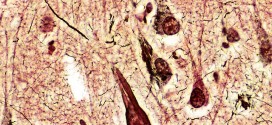

ACANTOSIS

La acantosis. Lesión epidérmica (piel) debida a un aumento de la multiplicación y aumento del grosor de la epidermis, hipertrofia de las células del cuerpo de Malpighi. Lesión histológica provocada por el aumento del número de células que constituyen la capa mucosa de la epidermis. Engrosamiento de la epidermis por hiperplasia del estrato de las células espinosas. Desarrollo hipertrófico de …

ACANTOLISIS

La acantolisis. Desprendimiento de las células del cuerpo mucoso de Malpighi (capa más interna de la epidermis formada por estratos basal y espinoso), caraterizada por disminución de su adherencia recíproca. La acantólisis consiste en la pérdida de conexión entre los queratinocitos de la epidermis como resultado de la destrucción de los desmosomas intercelulares que conlleva a la formación de hendiduras …